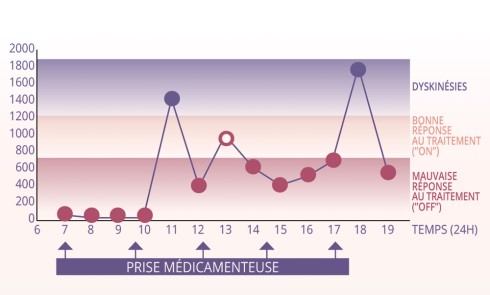

Recommandations pour la prise en charge au cabinet dentaire Identifier les patients (stade de la maladie, traitements suivis…) en se rapprochant...Anorexie mentale et érosion dentaire : l’orthodontiste au cœur du dépistage